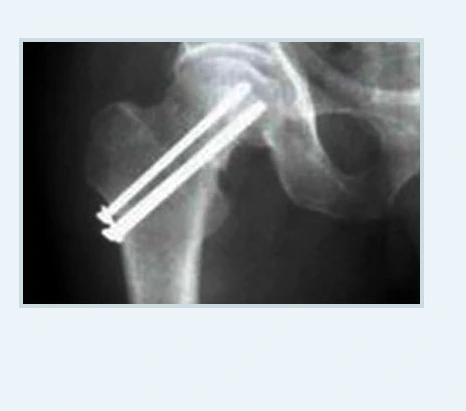

골절유합술.PNG 골절유합술 영상 사진

=> 골절 정도가 가볍거나 뼈의 상태가 양호한 경우에는 골절된 부위를 나사와 금속판을 이용해 고정하는 고관절 골절 유합술을 시행하며, 원래의 관절 기능을 회복시키면서 빠른 일상생활 복귀와 합병증 및 부작용 위험이 낮은 인공관절 치환술을 실시합니다